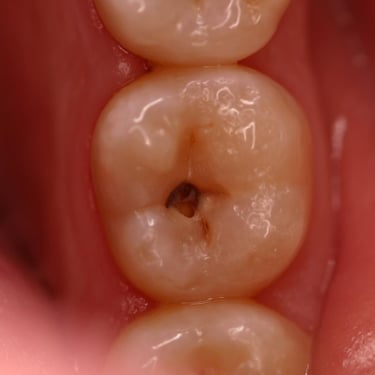

Pulpitis Reversible

La pulpitis reversible es una inflamación leve de la pulpa dental, generalmente causada por caries o una lesión menor.

Los pacientes suelen experimentar sensibilidad al frío o al calor, pero el dolor desaparece rápidamente.

Si se trata adecuadamente, la pulpa puede sanar sin complicaciones. Es importante acudir al dentista para evitar que progrese a una pulpitis irreversible.